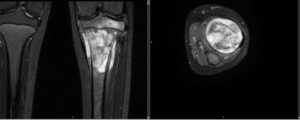

- Ressonância Magnética (RM): Fornece detalhes sobre a extensão do tumor e sua relação com os tecidos moles ao redor.

- Biópsia: Essencial para confirmar o diagnóstico. Uma amostra de tecido é removida e analisada em laboratório para determinar o tipo de sarcoma.